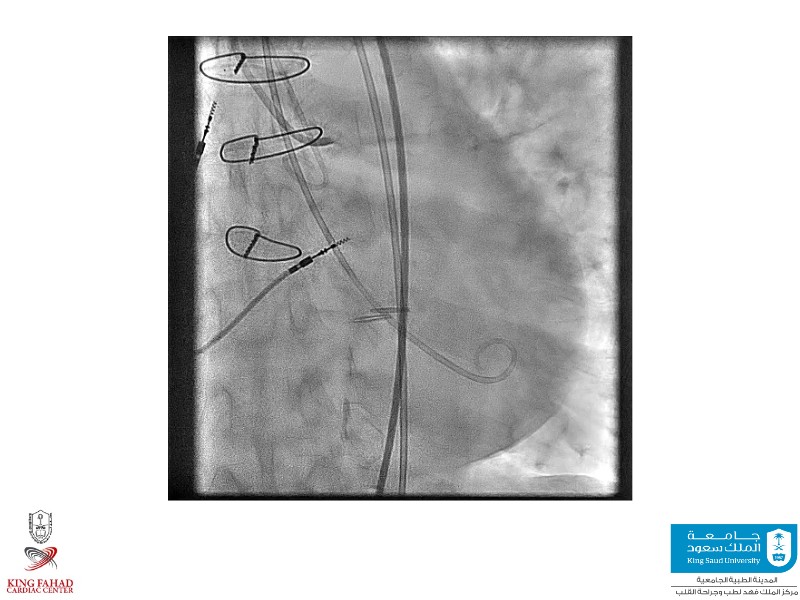

This session helps you anticipate and address complex scenarios such as mitral valve-in-valve, TAV-in-SAV, and valve-in-valve-in-valve procedures. Learn from expert case discussions that explore procedural strategies, technical challenges, and best practices to optimize outcomes in redo structural heart interventions.